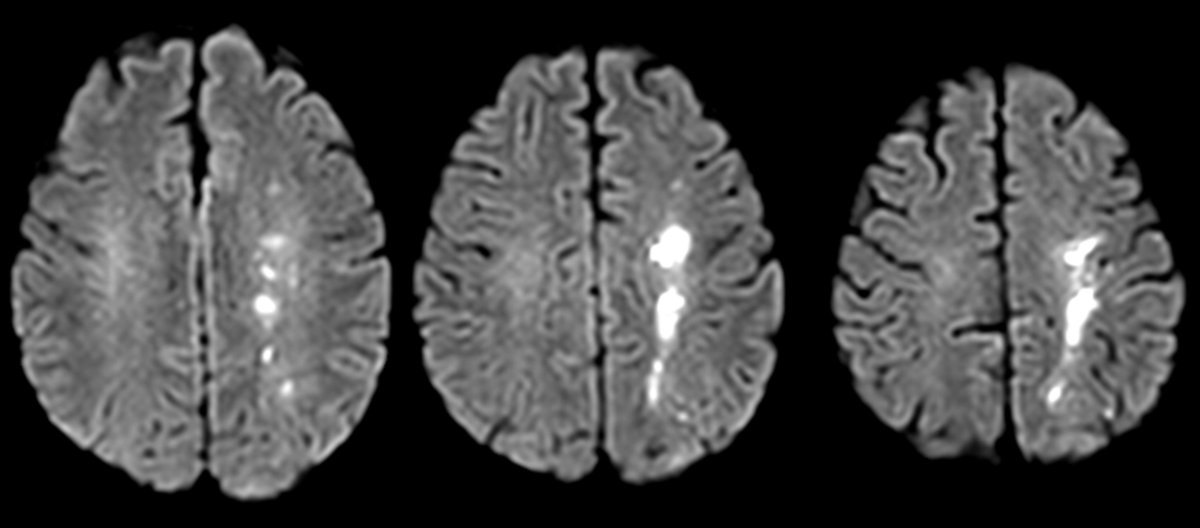

Finally published on Cell Death&Disease (@Nature group)! A comprehensive review I had the pleasure and the honor to write with prof. Paolo Calabresi (Università Cattolica del Sacro Cuore) and prof. @lvolpic (UAB).

🧠📚 #Neurology #Parkinson